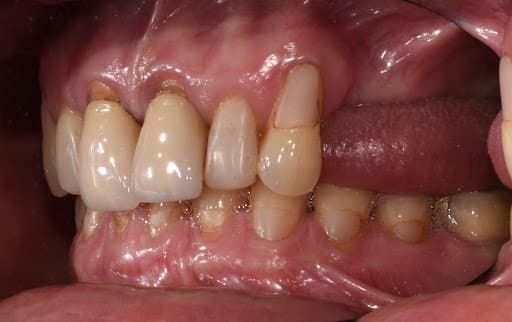

Lateral view of initial clinical situation.